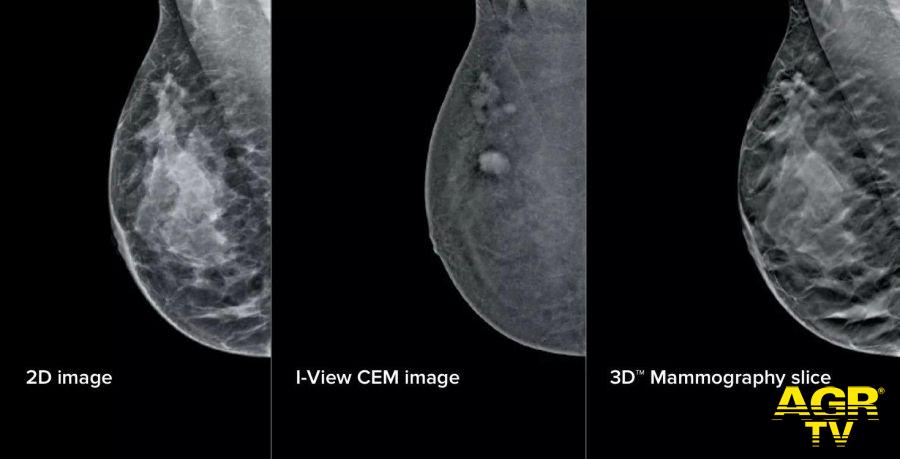

Roma, 22 aprile - All’Azienda Ospedaliera San Camillo Forlanini la mammografia diventa "intelligente". Grazie all'integrazione di IA e mammografi di ultima generazione, la UOSD Diagnostica per Immagini in Senologia ha messo a punto un intervento tecnologico profondo che coinvolge strumenti, software e flussi di lavoro, ottimizzando l'attività dei professionisti e rendendo i percorsi diagnostici più semplici e meno gravosi per le pazienti. La Breast Unit dell’ospedale romano risulta, ad oggi, l'unica struttura pubblica in Italia a vantare una configurazione così completa e all’avanguardia per quanto riguarda i mammografi del segmento.

Sul fronte della refertazione, è stata introdotta una nuova workstation con monitor ad altissima risoluzione e strumenti avanzati di analisi delle immagini. Un software dedicato consente di valutare in modo oggettivo la densità del tessuto mammario, un elemento importante perché associato al rischio di tumore al seno.

A questo si aggiunge un software che analizza struttura e densità del tessuto mammario, tecnologia di tomosintesi avanzata che riduce del 66% il numero di slice — le "fettine" spesse 1 mm di tessuto mammario acquisite dal mammografo — mantenendo le stesse informazioni diagnostiche. Meno immagini da scorrere significa meno affaticamento: una riduzione del carico cognitivo per il radiologo stimata intorno al 13%, con benefici concreti soprattutto nelle sessioni di lettura multipla.

A supporto dei medici è stato integrato anche un sistema di intelligenza artificiale che evidenzia automaticamente le aree sospette sulle singole slices, come microcalcificazioni o alterazioni del tessuto, e fornisce indicazioni utili per la priorità di lettura. Studi preliminari indicano un miglioramento della capacità di individuare lesioni fino al 9%.